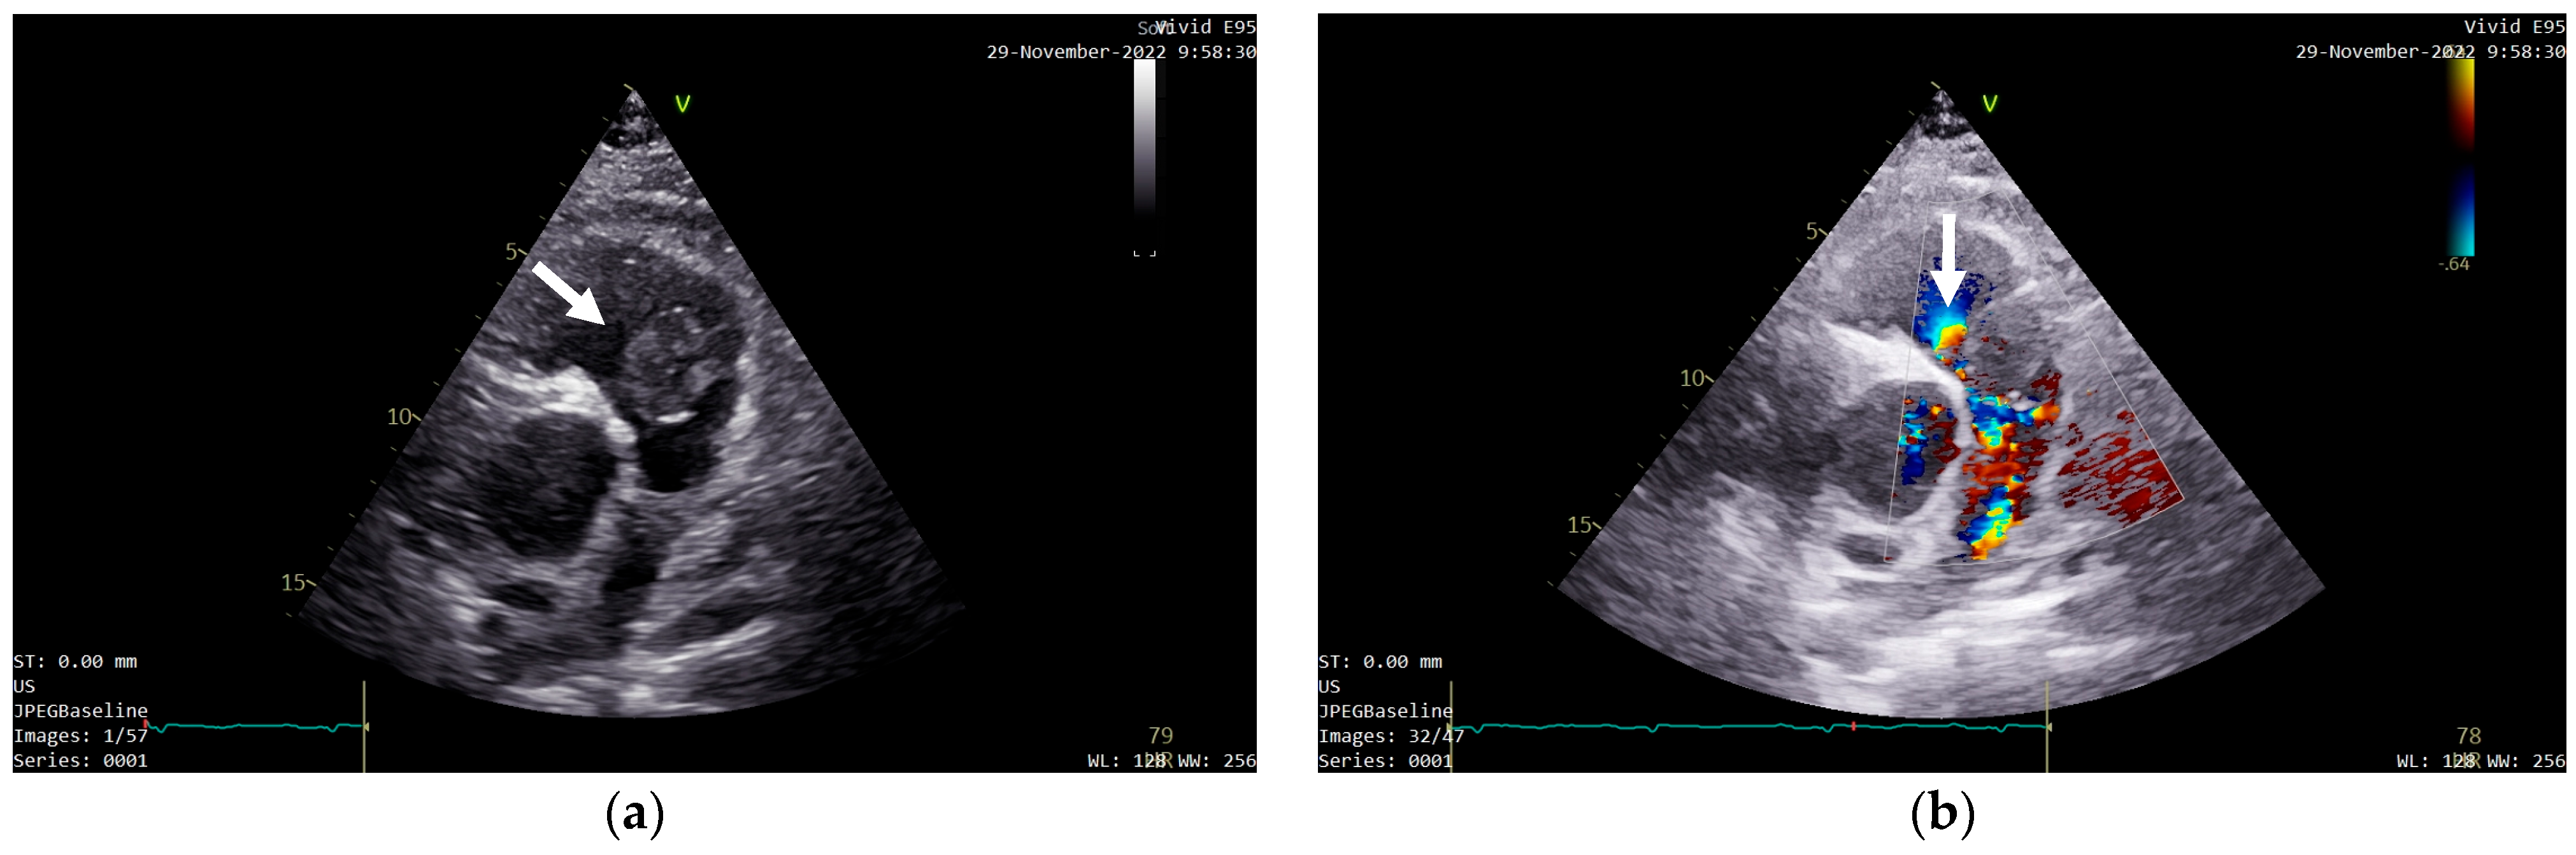

Follow-up whole-body PET-CT was performed 3 months after the surgical intervention. Adjacent to the right ventricle infundibulum, a 30/19 mm area corresponding to the pericardium was observed. It presented minimum calcification, thin minimally 18F-FDG fluorodeoxyglucose (18F-FDG) active margins, and no other fixation zones (Figure 8a). Considering the modest 18F-FDG fixation, the area was interpreted as an encapsulated effusion, and CMR reevaluation along with periodical PET-CT monitoring of the lesion was recommended. Slight 18F-FDG fluorodeoxyglucose (18F-FDG) fixation was also observed at the sternum level, given the recent sternoraphy, but no distant metastases were found (Figure 8b).

Figure 8. 18F-FDG fluorodeoxyglucose (18F-FDG) PET-CT showing: (a) an encapsulated effusion adjacent to the right ventricle infundibulum (white circle) with minimum calcification, thin minimally active margins, and no other 18F-FDG fixation zones at this level; slight 18F-FDG fixation at the sternum level due to recent sternoraphy; (b) no distant metastases on the whole-body examination.